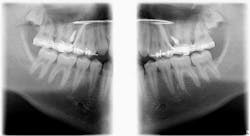

Case report

A healthy 15-year-old male presents to the clinic with an anterior open bite. His case is outlined in the figures below.

The patient in the above case report is still in active treatment. Now that successful maxillary posterior intrusion has been accomplished, the remaining full, fixed orthodontic appliances can be placed. The TPA can be removed and the molar intrusion will be held for the remainder of treatment with a ligature tie placed from the first molar to the TADs. The TADs will be kept in place for the remainder of treatment to maintain the stability of the intrusion as bone remodeling occurs.